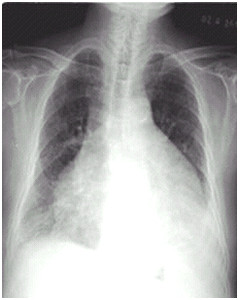

03卷-5.女性,63岁,咳嗽、咳痰、胸闷2月,伴下肢浮肿4天。诊断(本题满分2.00分)

A.靴形心

B.正常心脏

C.普大型心脏

D.梨形心

本题答案:C

题目解析:

【该题针对“ X线-心脏增大(尖瓣型、主动脉型和普大型) ”知识点进行考核】